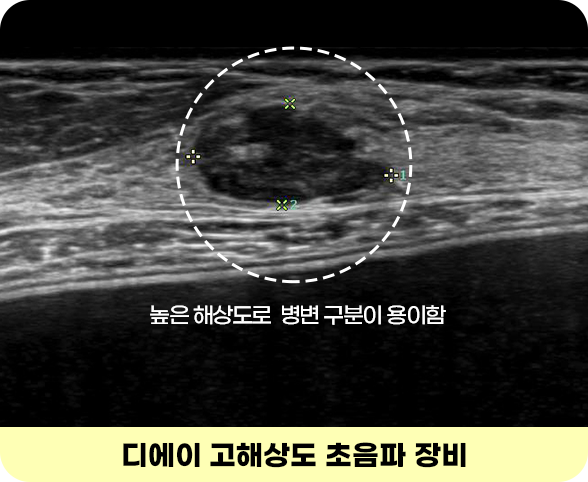

고해상도 초음파

일반 초음파는 해상도가 낮아 진단이 어려우나,

디에이 고해상도 초음파는 미세 병변을 찾아

정확한 진단과 예방 케어가 가능합니다.